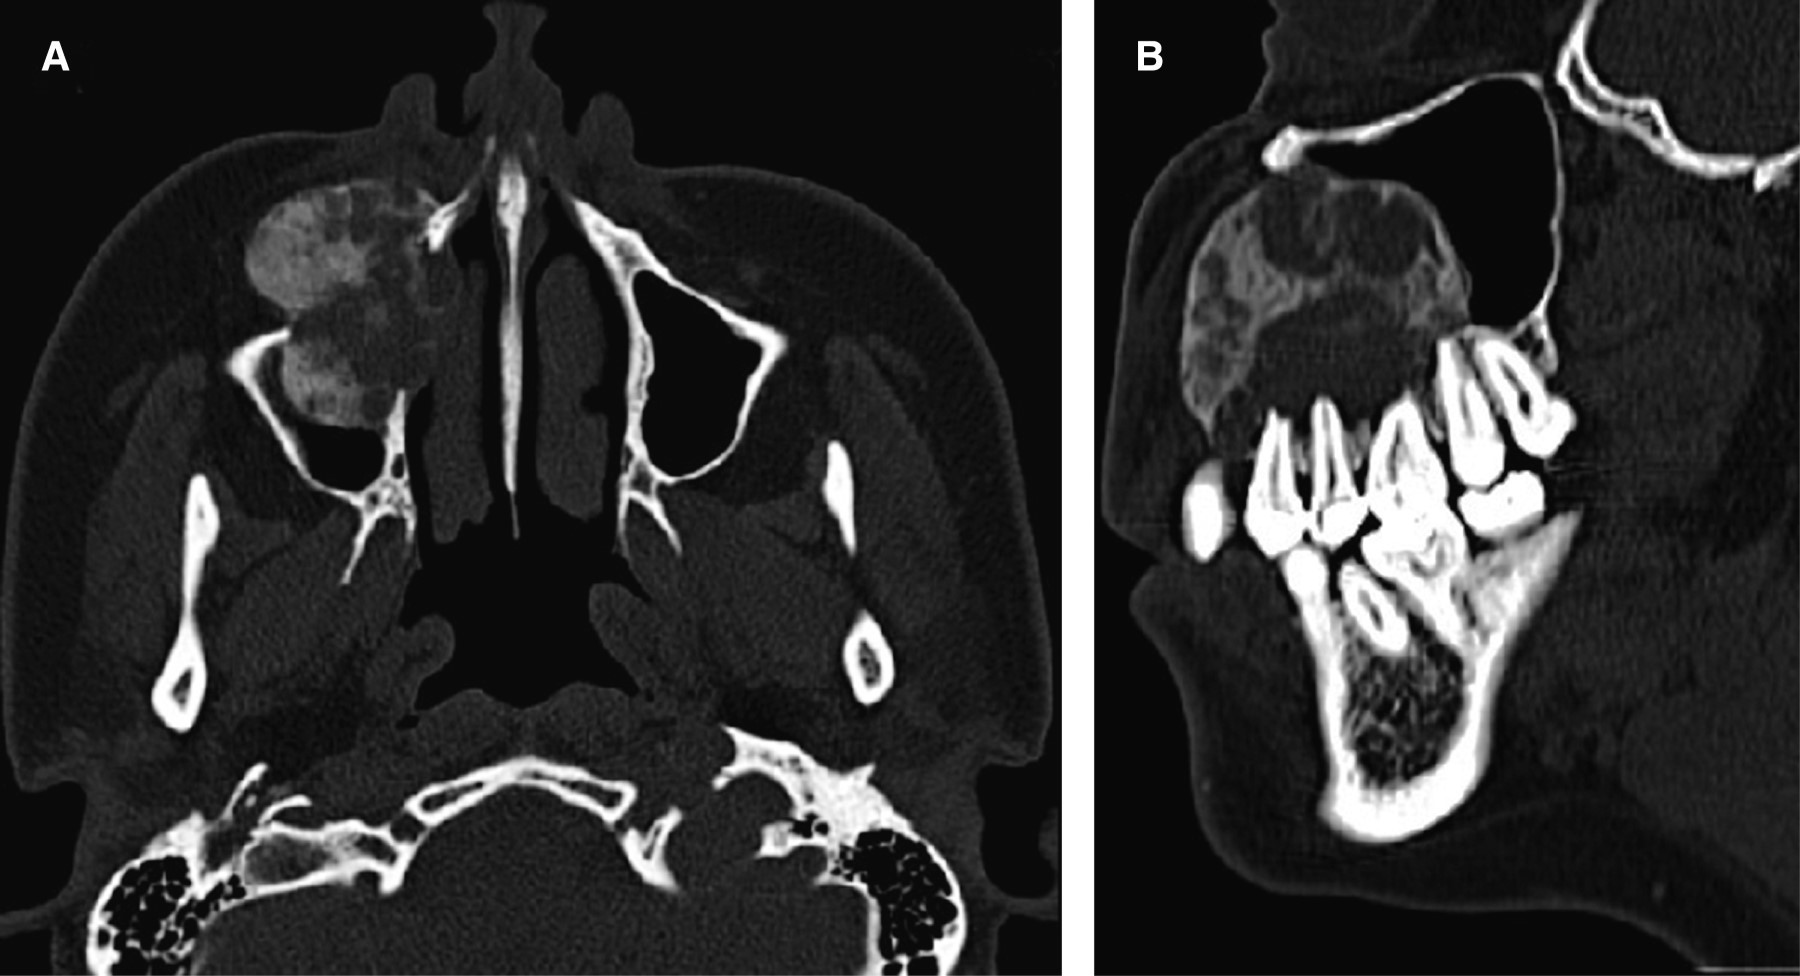

A la exploración clínica presentaba ligera asimetría facial a expensas de aumento de volumen en región nasogeniana derecha de aproximadamente 4.0 × 4.0 cm, sin cambios en la piel. Intraoralmente se observó pérdida de fondo de repliegue mucogingival debido al aumento de volumen que va desde la zona cercana a la apófisis triangular maxilar hasta el borde alveolar cercano al primer premolar de lado derecho. Bien delimitado, superficie lisa, mismo color que las mucosas adyacentes, de consistencia firme, asintomático a la palpación, con extrusión de primer y segundo premolar. En la tomografía axial computarizada simple se muestra una lesión mixta: zonas hiperintensas e hipodensas a tejido blando, la cual se encuentra ocupando el maxilar de lado derecho. Se extiende por el cuerpo, la apófisis piramidal, gran parte el seno maxilar y región alveolar desde canino a primer molar ipsilateral, con desplazamiento de los mismos, expansión y perforación de la cortical vestibular (Figura 1). De acuerdo con las características clínicas y de imagen, el diagnóstico presuntivo corresponde a GCCG, y se indica toma de biopsia incisional, la cual resulta compatible con GCCG, para descartar tumor pardo del hiperparatiroidismo se solicitan niveles de parathormona, la cual se encuentra dentro de parámetros normales.

Figura 1